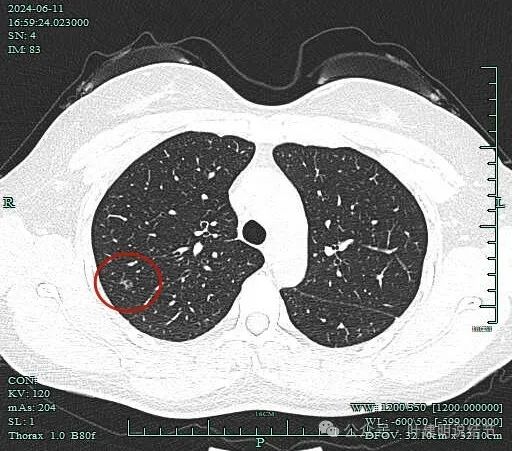

先看2024年6月的影像:

病灶出现,磨玻璃密度,似乎伴小空泡的样子,整体轮廓较清。